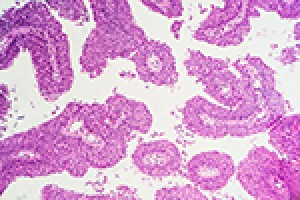

A team led by Johns Hopkins researchers has discovered a biochemical signaling process that causes densely packed cancer cells to break away from a tumor and spread the disease elsewhere in the body.The team also reported that the combined use of tw...